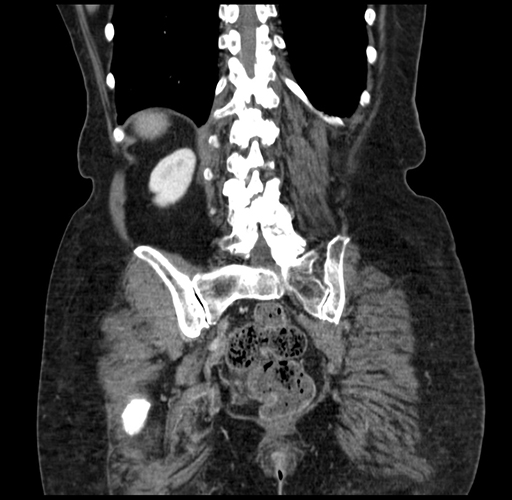

Coronal Venous